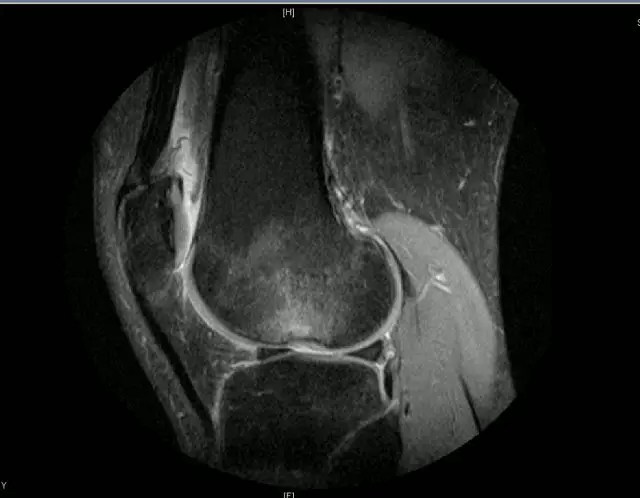

关节扭伤常常导致膝关节相关韧带结构的损伤,如何及时发现这些损伤并进行相关的治疗,是我们临床医师常常面临的问题,除了相关病史、临床体征之外,磁共振扫描也是重要的诊断依据

膝关节的解剖结构

正常的膝关节

韧带结构:形态,张力,质地,连续性

半月板:完整性,形态,质地